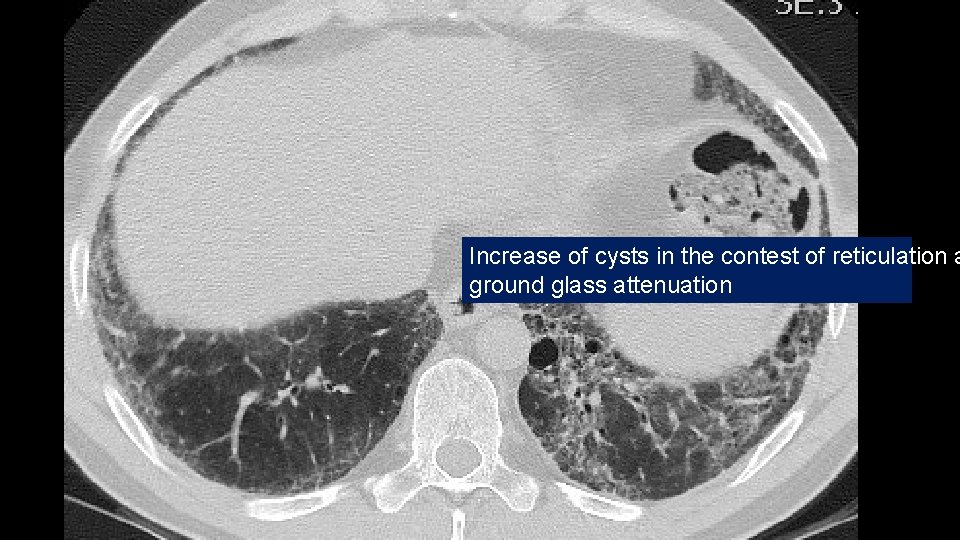

Increase of cysts in the contest of reticulation a ground glass attenuation

Progressive decrease of subpleural sparing

VATS Bx: Fibrosis with honeycombing, in some areas patchy